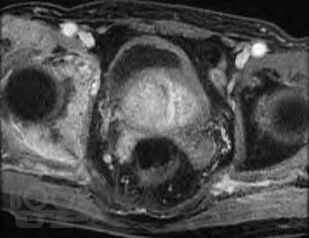

Метастазы в костную ткань у пациентов при онкоурологической патологии

Учебное пособие подготовлено в соответствии с требованиями ФГОС ВО 3++ по программе подготовки кадров высшей квалификации в ординатуре по специальности 31.08.68 Урология (2014). В пособии на современном уровне излагаются механизмы распространения метастазов в костную ткань, их диагностика и лечение у пациентов с онкоурологической патологией. Пособие содержит рисунки из открытых источников интернета.